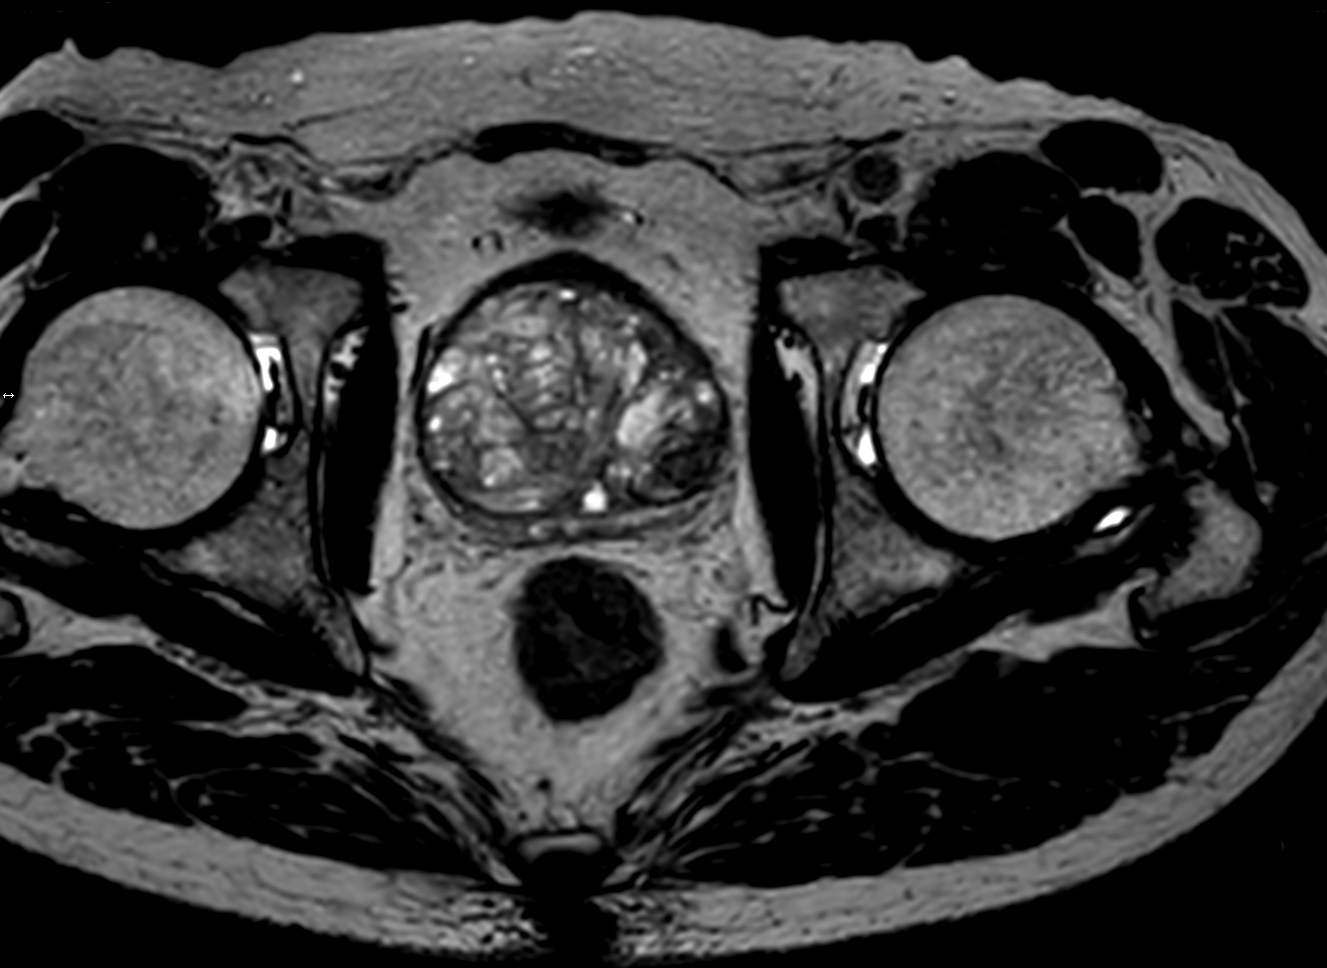

Multi-phase, contrast-enhanced prostate imaging

Patient with a prostate lesion. The ExamCard includes techniques for 3D imaging (PelvisVIEW, eTHRIVE) allowing for multiple image directions in one single scan, efficient fat-free imaging over large field-of-views (mDIXON XD), a multi-phase contrast-enhanced sequence (4D FreeBreathing) to improve imaging confidence and Compressed SENSE to accelerate the entire exam.

3D T2w TSE PelvisVIEW Compressed SENSE

3D T2w TSE PelvisVIEW (reformat) Compressed SENSE